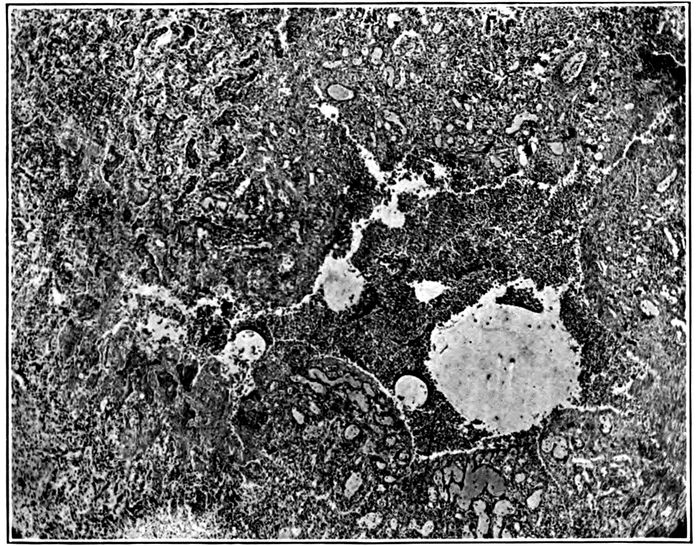

| 11. | Suppurative interstitial pneumonia | 212 |

| 12. | Suppurative interstitial pneumonia | 216 |

| 13. | Suppurative interstitial pneumonia showing a dilated lymphatic | 217 |